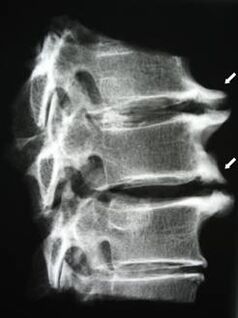

In the initial stages, osteochondrosis is detected with the help of MRI.Later, the pathology can be diagnosed using radiography.On the X-ray of the cervical spine, a decrease in the distance between the vertebrae, pathological changes in the facet joints and osteophytosis are noted.

| Cervical osteochondrosis | The appearance of pathological changes in one or more spinal motor segments.Impaired mobility of the spine, development of myofascial pain syndromes and pinching of spinal roots | Pain, paresthesia and movement disorders in the cervical region, which spread to the back of the head and upper limbs.Detection of characteristic changes in the spine on MRI and X-rays (osteophytes, reduced distance between the vertebrae, signs of damage to the intervertebral joints) |